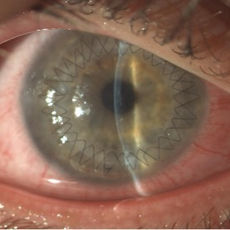

Cataratta bianca

IOL in camera anteriore